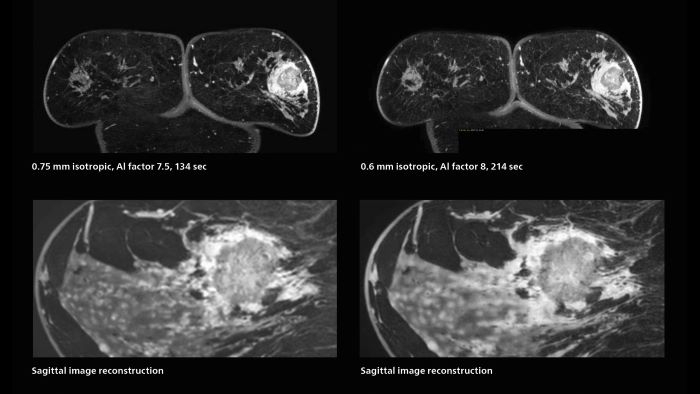

3D MRI of breast cancer

Scanning was performed with two different voxel sizes. AI enabled volume MRI allows image reconstruction in other directions. Biopsy revealed invasive ductal carcinoma in this patient. Performed on Elition X.

Fast AI-enabled MRI of breast cancer: comparing 3D acquisitions with 0.75 mm and 0.6 mm isotropic voxels.

Speed and high image quality are also important factors determining the diagnostic value of breast MRI. “When the spatial resolution is not high enough for making the diagnosis of breast cancer, a very difficult decision must be made,” says Dr. Katahira. “Since SmartSpeed now allows us to increase the resolution, we can often easily provide a confident answer. In the past with SENSE we used 1.2 mm isotropic voxels in breast imaging after contrast admission. With Compressed SENSE that is 0.8 mm. Now with SmartSpeed we can acquire 0.6 mm isotropic voxels and the images are so clear that even tiny details are clearly visible.”